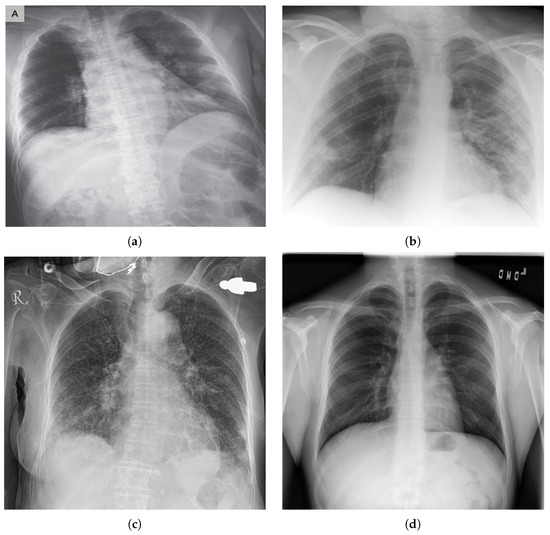

COVID-19 typically causes pneumonia in human lungs, which can be detected in X-ray images (see Figure 1). Datasets of people with pneumonia inflicted by COVID-19, as well as people with pneumonia inflicted by other diseases, became available online, thus enabling the possibility to create deep learning networks that can differentiate between X-ray images of people with COVID-19 and people who do not have the disease. The dataset used in this study is publicly available and can be accessed online (https://github.com/ieee8023/covid-chestxray-dataset (accessed on 12 February 2021)). Using deep learning can help save time in testing for COVID-19 in time-critical situations, which could potentially save more lives. Having results obtained from AI can help clinicians validate their results as well as make better-informed decisions. The structure of this paper is as follows:

Figure 1. Chest X-ray of a person (a) with a COVID-19, (b) with COVID-19 pneumonia, (c) with pneumonia, and (d) a normal case.